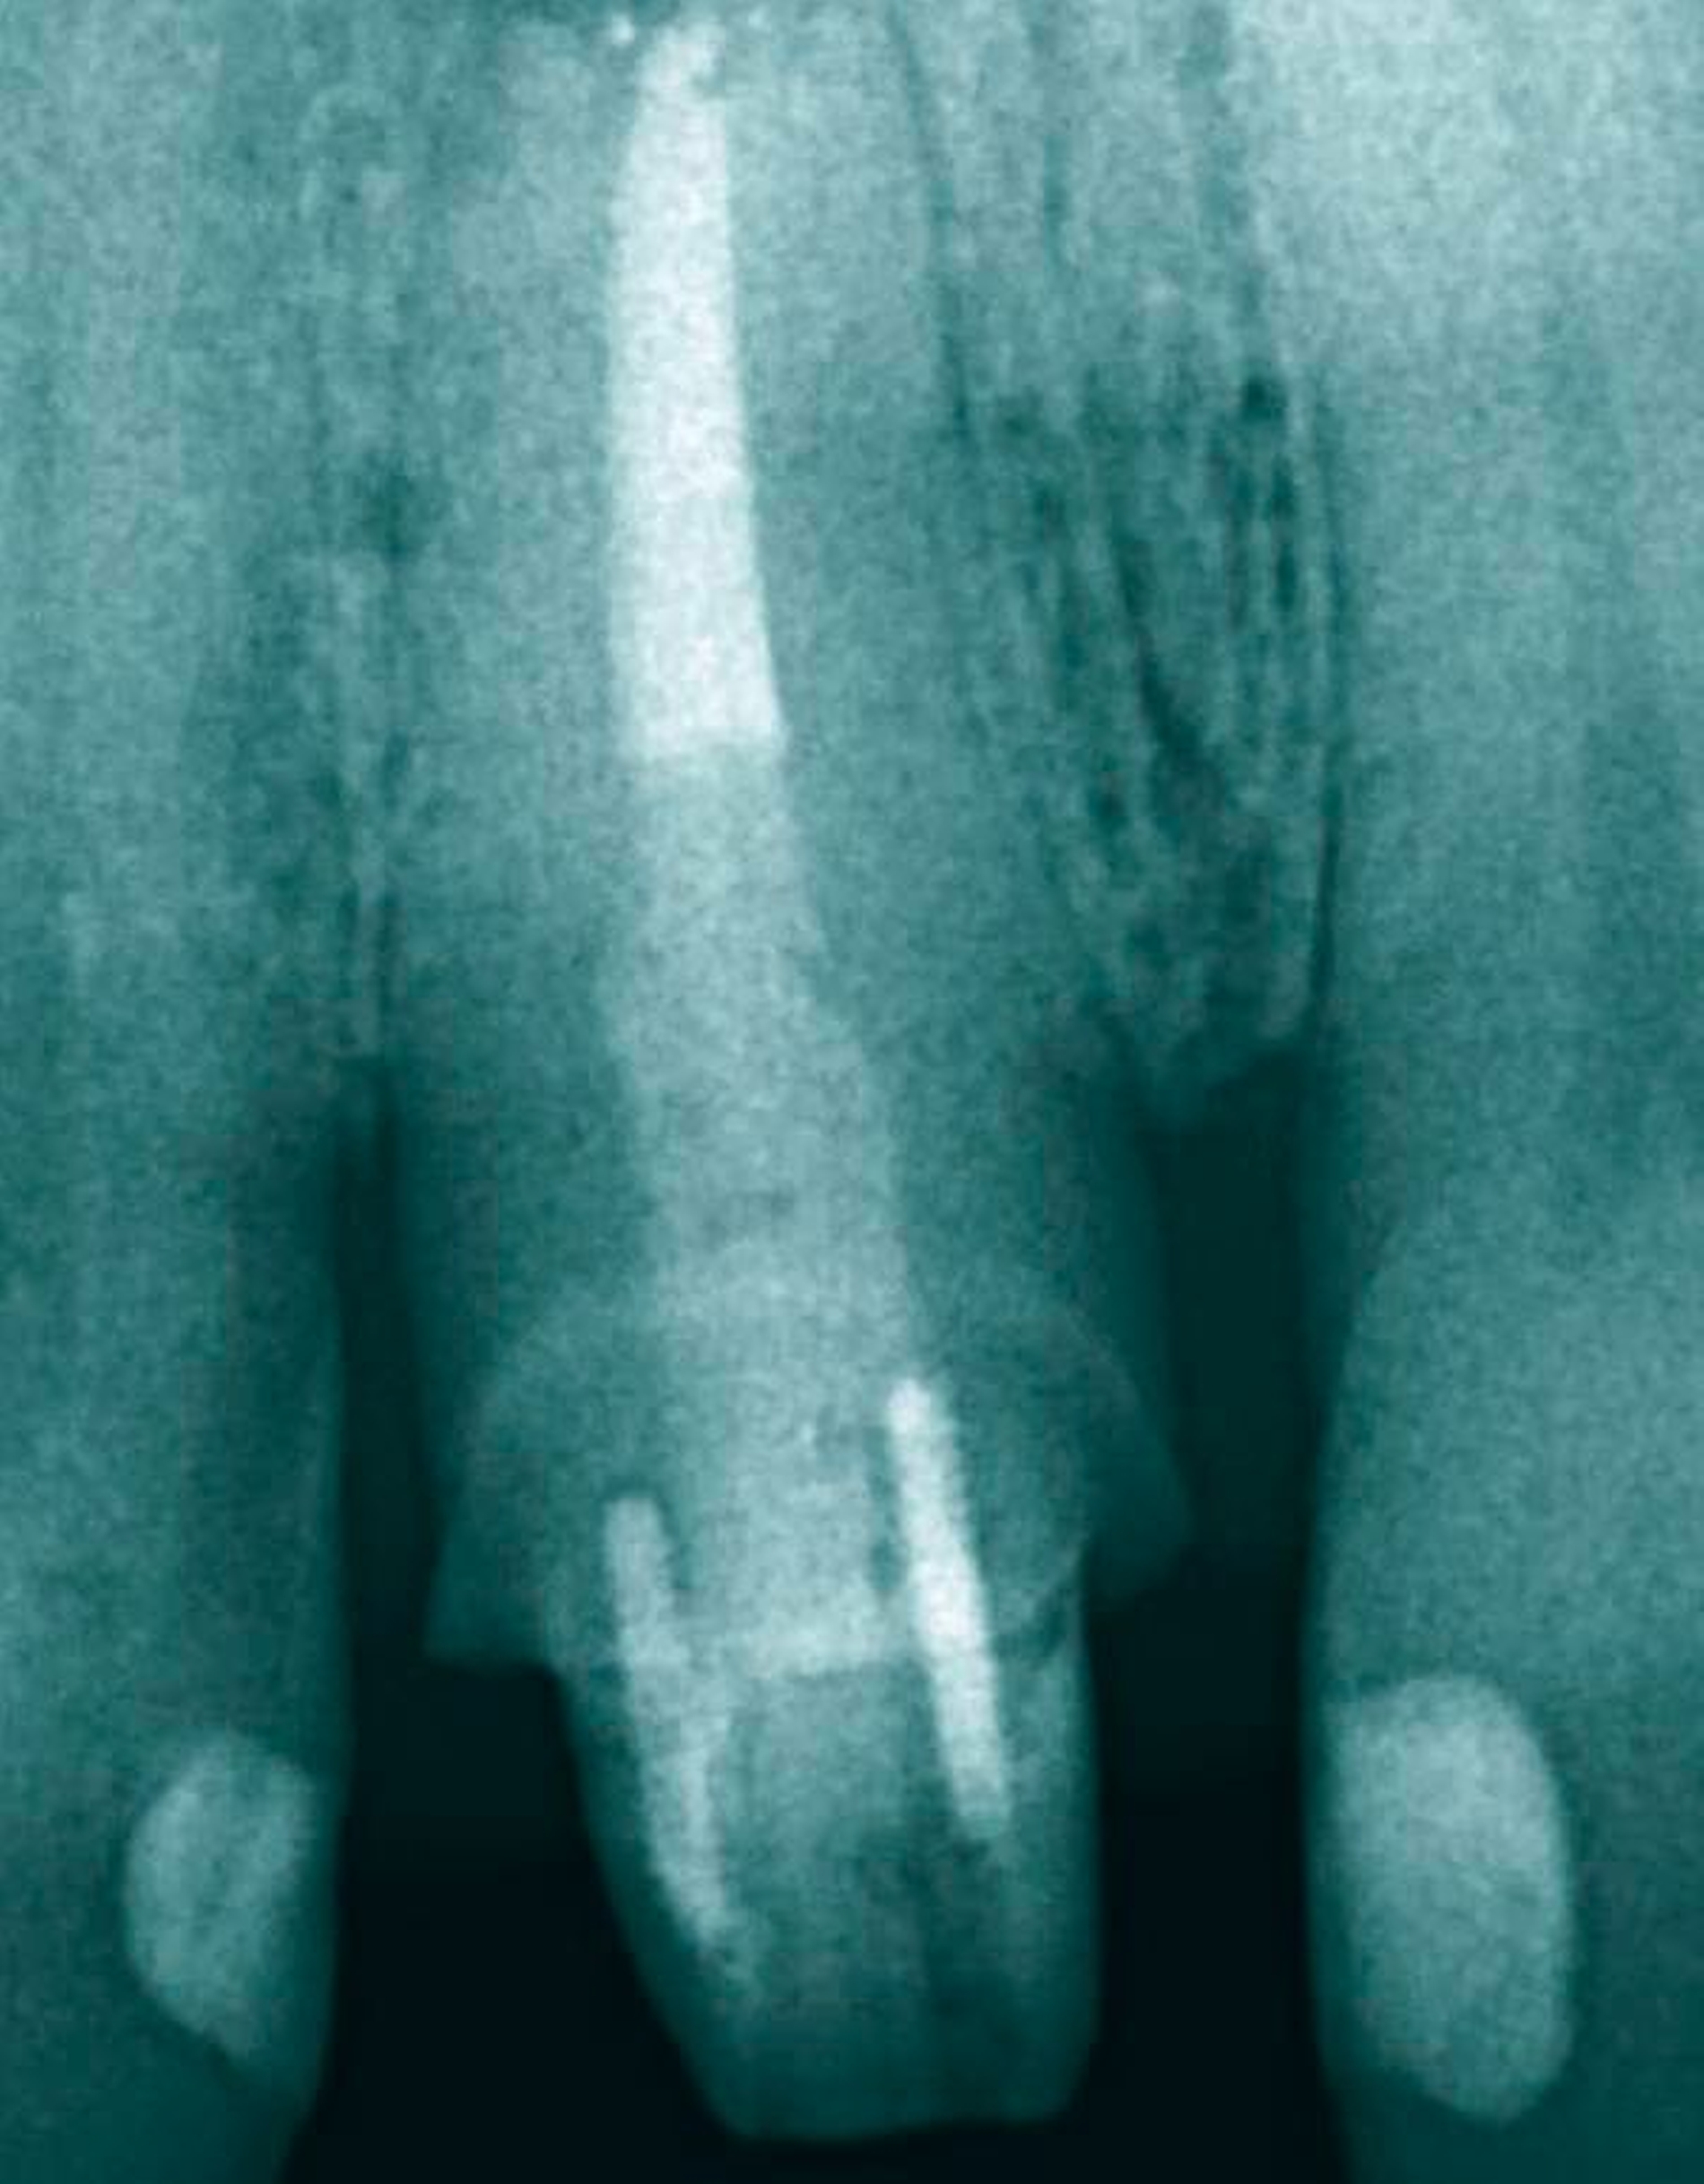

In der ersten Therapiesitzung erfolgte – nach Isolierung mit Kofferdam – die Trepanation des Zahnes und die Stiftentfernung mit Ultraschallinstrumenten. Im Anschluss wurden die drei gefüllten Kanäle revidiert, der vierte, nicht abgefüllte, mesiobukkale Kanal dargestellt und präpariert. Die elektronische Längenmessung ergab 14,5 mm für den mesiobukkalen Kanal, 17,0 mm für den mesiolingualen, 15 mm für den distobukkalen und 16 mm für den distolingualen. Aufgrund der großen initialen Kanaldurchmesser und der guten Einsicht bis ins periapikale Gewebe (Abbildung 2) wurde auf eine Längenmessaufnahme verzichtet. Die Desinfektion erfolgte mit Natriumhypochlorid (NaOCl) 5 Prozent und EDTA 17 Prozent, sowie Schallaktivierung mittels EDDY-Spitzen (VDW, München). Das Wurzelkanalsystems wurde manuell mit K-Feilen bis IS0 70 präpariert. Es folgte eine medikamentöse Einlage mit AH Temp (DentsplySirona, Bensheim). Danach wurde eine Aufnahme zur Kontrolle der vollständigen Guttapercha-Entfernung und der suffizienten Einbringtiefe des Kalziumhydroxids angefertigt (Abbildung 3).